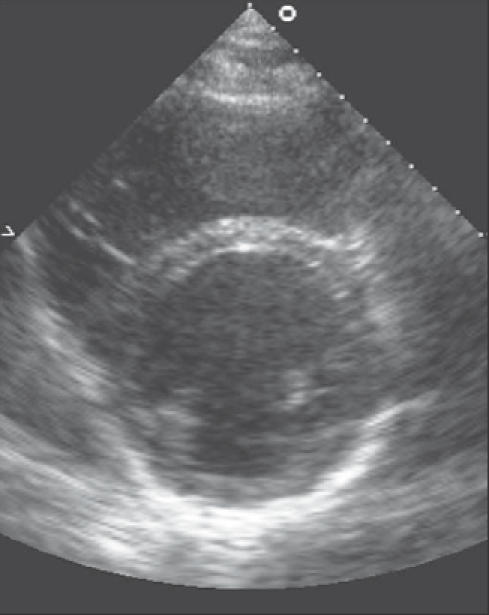

Una diagnosi formale richiede la presenza di sintomi tipici (dispnea, astenia, edemi) accompagnati da segni clinici (tachicardia, tachipnea, turgore giugulare) e la conferma di una sottostante causa cardiaca, identificata tramite imaging (ecocardiografia) o livelli elevati di peptidi natriuretici.2

L’ecocardiografia colordoppler è lo strumento principe per definire la frazione di eiezione e le alterazioni valvolari e cardiache.